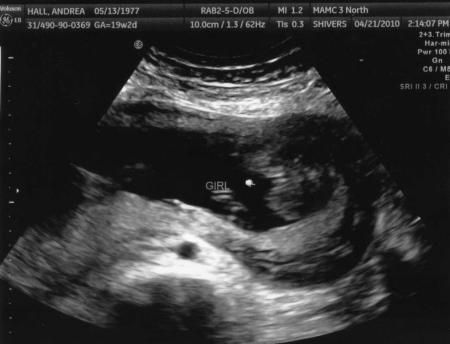

Jetzt faellt mir gerade ein, dass ich euch ja die Bilder von unserem Feinultraschall in der 20. Woche noch vorenthalten habe. Die will ich jetzt noch schnell schicken zur Vervollstaendigung. Auf dem ersten hier, finde ich es sooo suess, weil sie richtig laechelt und so aussieht, als ob sie winkt. Freunde und Familie sagen da jetzt schon, dass die Gesichtszuege aussehen, wie vom Papa. ;-)

Bild zu Nachtrag Bilder zu unserem Feinultraschall - Forum für September - Mamis